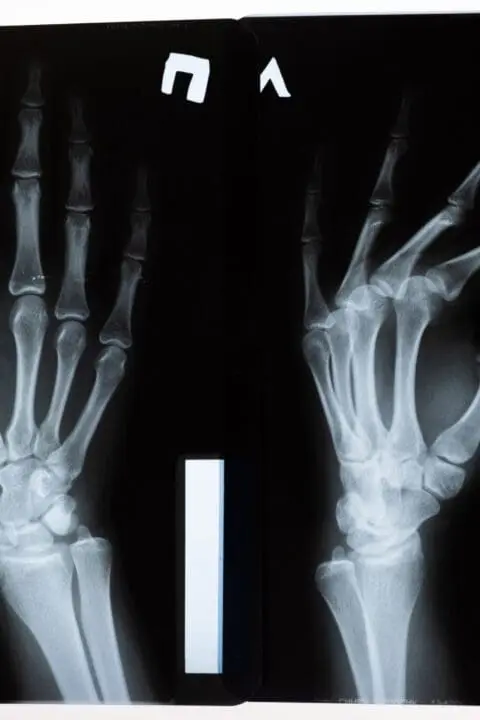

Bone Sarcoma